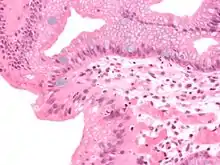

High-magnification micrograph of Barrett's esophagus showing the characteristic goblet cells, Alcian blue stain

The presence of goblet cells, called intestinal metaplasia, is necessary to make a diagnosis of Barrett's esophagus. This frequently occurs in the presence of other metaplastic columnar cells, but only the presence of goblet cells is diagnostic. The metaplasia is grossly visible through a gastroscope, but biopsy specimens must be examined under a microscope to determine whether cells are gastric or colonic in nature. Colonic metaplasia is usually identified by finding goblet cells in the epithelium and is necessary for the true diagnosis.

Many histologic mimics of Barrett's esophagus are known (i.e. goblet cells occurring in the transitional epithelium of normal esophageal submucosal gland ducts, "pseudogoblet cells" in which abundant foveolar [gastric] type mucin simulates the acid mucin true goblet cells). Assessment of relationship to submucosal glands and transitional-type epithelium with examination of multiple levels through the tissue may allow the pathologist to reliably distinguish between goblet cells of submucosal gland ducts and true Barrett's esophagus (specialized columnar metaplasia). The histochemical stain Alcian blue pH 2.5 is also frequently used to distinguish true intestinal-type mucins from their histologic mimics. Recently, immunohistochemical analysis with antibodies to CDX-2 (specific for mid and hindgut intestinal derivation) has also been used to identify true intestinal-type metaplastic cells. The protein AGR2 is elevated in Barrett's esophagus[17] and can be used as a biomarker for distinguishing Barrett epithelium from normal esophageal epithelium.[18]